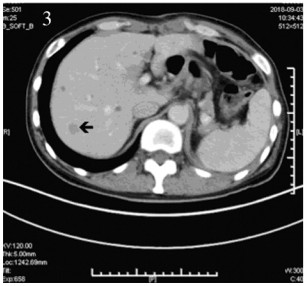

2018年9月1日患者入院接受术后辅助化疗,治疗前进行基线评估,2018年9月3日上腹CT:肝脏多发转移性病灶,见图 3。2018年9月1日乳酸脱氢酶(lactate dehydrogenase, LDH)171 u/L。依据2009版上呼吸道消化道黑色素瘤AJCC分期,患者诊断为PMME ⅣC期。因患者单肾,为保护患者肾功能,2018年9月3日、2018年9月25日开始两疗程替莫唑胺(300 mg, qd, d1~5)+恩度(15 mg, qd, d1~14)q3w联合治疗,而未加入铂类化疗,化疗后无明显不良反应。两疗程后评估,2018年10月17日胸部CT示T9、10椎体及T12密度不均匀降低,考虑转移性病变,见图 4,此时LDH 173 u/L,考虑患者出现新发骨转移,评估疾病进展(progressive disease, PD),更改治疗方案。定期行唑来膦酸骨修复治疗。